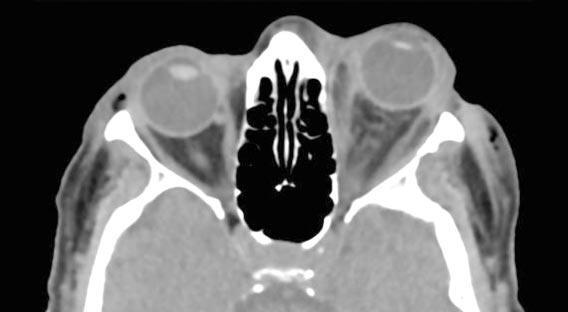

El paciente se interna para control estricto de la complicación intraoperatoria y evaluación cardiológica. Se solicita una TC de órbitas que evidencia aumento del espesor de partes blandas preseptales derechas con algunas burbujas aéreas adyacentes, en probable relación al antecedente quirúrgico, e imagen espontáneamente densa de localización extraconal que mide aproximadamente 2,5 cm x 0,7 cm en topografía inferolateral de la órbita derecha, de aspecto hemático, con discreto engrosamiento del músculo recto externo derecho en íntimo contacto con el hematoma descrito ( Imagen F ). Se interpreta como hematoma subperióstico secundario a la inyección temporal inferior para el bloqueo anestésico.

Imagen F: TC en corte coronales que evidencia imagen espontáneamente densa de localización extraconal que mide aproximadamente 2,5 cm x 0,7 cm en topografía inferolateral de la órbita derecha, de aspecto hemático, con discreto engrosamiento del músculo recto externo derecho en íntimo contacto con el hematoma descrito.

Posteriormente, una vez estabilizado el cuadro, se solicitó TC de cerebro y órbita de control donde se evidenciaba: contusión de partes blandas periorbitaria derecha con extensión maxilar y parietal homolateral, alteración de la grasa orbitaria intra y extraconal asociada a la presencia de líquido y/o sangre, engrosamiento del músculo recto interno, leve proptosis ocular derecha, trazos de fractura en la pared interna y piso de la órbita con herniación grasa orbitaria y velamiento del seno maxilar derecho, compatible con hemoseno, extendiéndose hacia coana homolateral y cavum ( Imagen J ).

Imagen J: TC cortes coronales que evidencian en OD alteración de la grasa orbitaria intra y extraconal asociado a presencia de líquido y/o sangre, engrosamiento del músculo recto interno, leve proptosis ocular y trazo fracturario en piso de la órbita con velamiento del seno maxilar compatible con hemoseno.